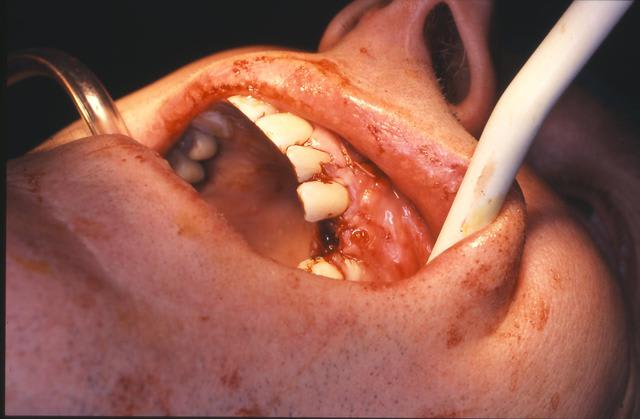

un cas dont j'avais discuté ailleurs avec amibien qui m'avait reproché de ne pas avoir fait la pose en même temps en juin dernier

la pose est de jeudi dernier mon apn est en panne, photo avec le portable, desolé pour le sang mais quand cela saigne il n'y a pas d'échec

Ne vous inquiétez pas je ne pense pas d'autres cas